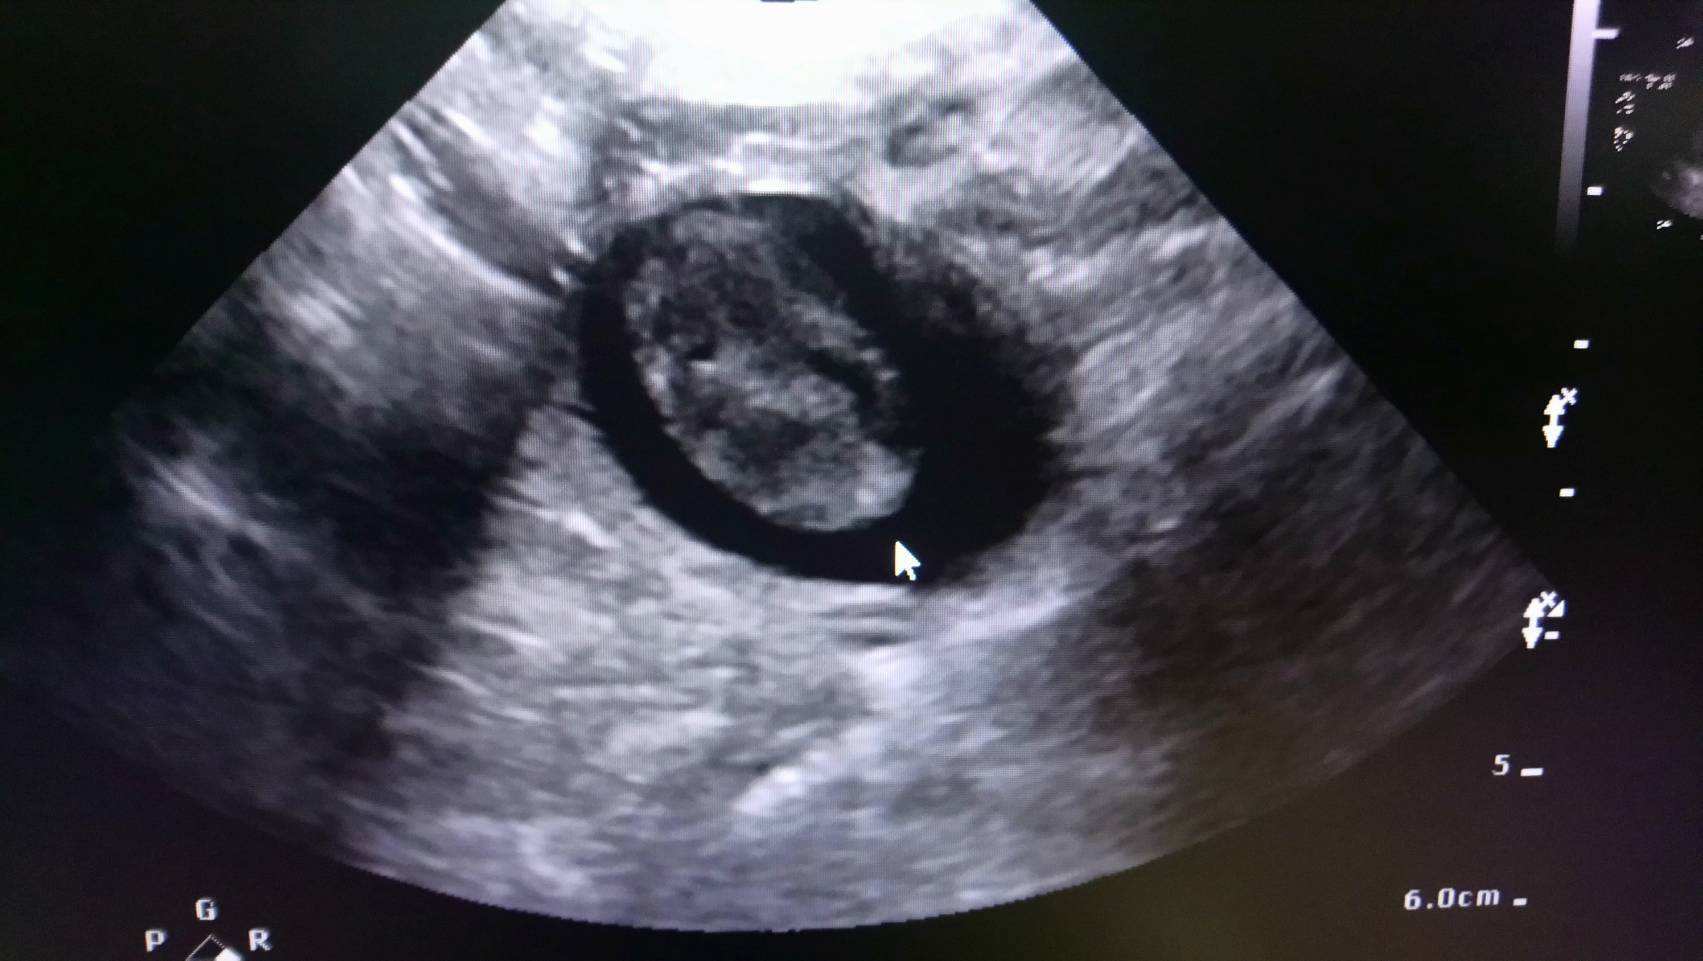

主題: 車禍重傷的小枳第三階段醫療費用 申請者姓名: 王昀 花色: 申請日期: 2018-03-04 05:51:39 申請者部落格: 申請者臉書網址: https://www.facebook.com/Wangyunpet 所在縣市/合作醫院: 台北市/澄諾動物醫院 治療費用: 18153元 需求人數: 39人 已結案 (2024-06-01 13:15:03) 報名人員: 小貍仔(已付款)、MinCat(已付款)、Yvonne(已付款)、薇薇安(已付款)、Tracy Hsu x2(已付款)、Meditator(已付款)、灰色貓(已付款)、Elsa Tu(已付款)、Wenny Chen(已付款)、Eve(已付款)、洪凱威 x2(已付款)、小康(已付款)、Nina(已付款)、碰碰(已付款)、Shu-Han Pan(已付款)、jill(已付款)、miraai x2(已付款)、Sophia x10(已付款)、Sophia x9(已付款)、 候補人員: 動物病情說明: 遭遇車禍受重傷的小枳經過疝氣手術保住性命後,接著在專業的骨科醫院進行股骨頭切除手術後,主治醫師顧慮貓咪對陌生環境較為敏感的個性,所以術後將小枳帶回原醫療院所休養,預計手術傷口復原期為14天,但在傷口復原期間,主治醫師發現小枳的尿液帶有黑褐色的碎屑,於是為小枳進行超音波檢查,檢查結果發現小枳的膀胱有幾個血塊,因此主治醫師在照顧小枳手術傷口的同時也為小枳進行膀胱血塊的清除。

膀胱血塊的清除是漸進、緩慢的工作,不是一時半刻可以見效的,除了投藥之外,更重要的是補充足夠的水分以增加小枳的排尿量,讓血塊隨著尿液排出體外,主治醫師利用各種方式增加小枳的喝水量,比如在罐頭裡加水、給予泥狀的食物等等。小枳在醫生的悉心照顧下,排尿量增加,膀胱血塊逐漸縮小。小枳原本14天的休養期也因此拉長到25天,在小枳膀胱血塊削減到大約只剩下百分之十時,因為膀胱血塊的消除沒有一定的時間,醫生也無法斷言膀胱血塊完全消除需要多久的時間,因此決定讓小枳出院,但醫生有叮囑我要注意觀察小枳排尿情況,如小枳排尿量減少或尿液中帶有黑褐色碎屑要立即帶小枳回診。